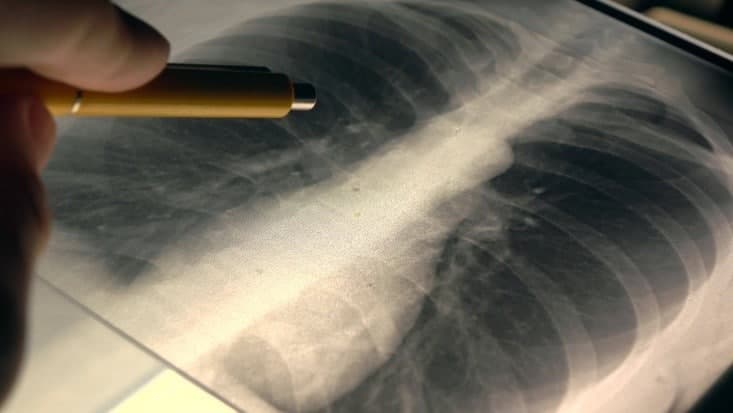

103